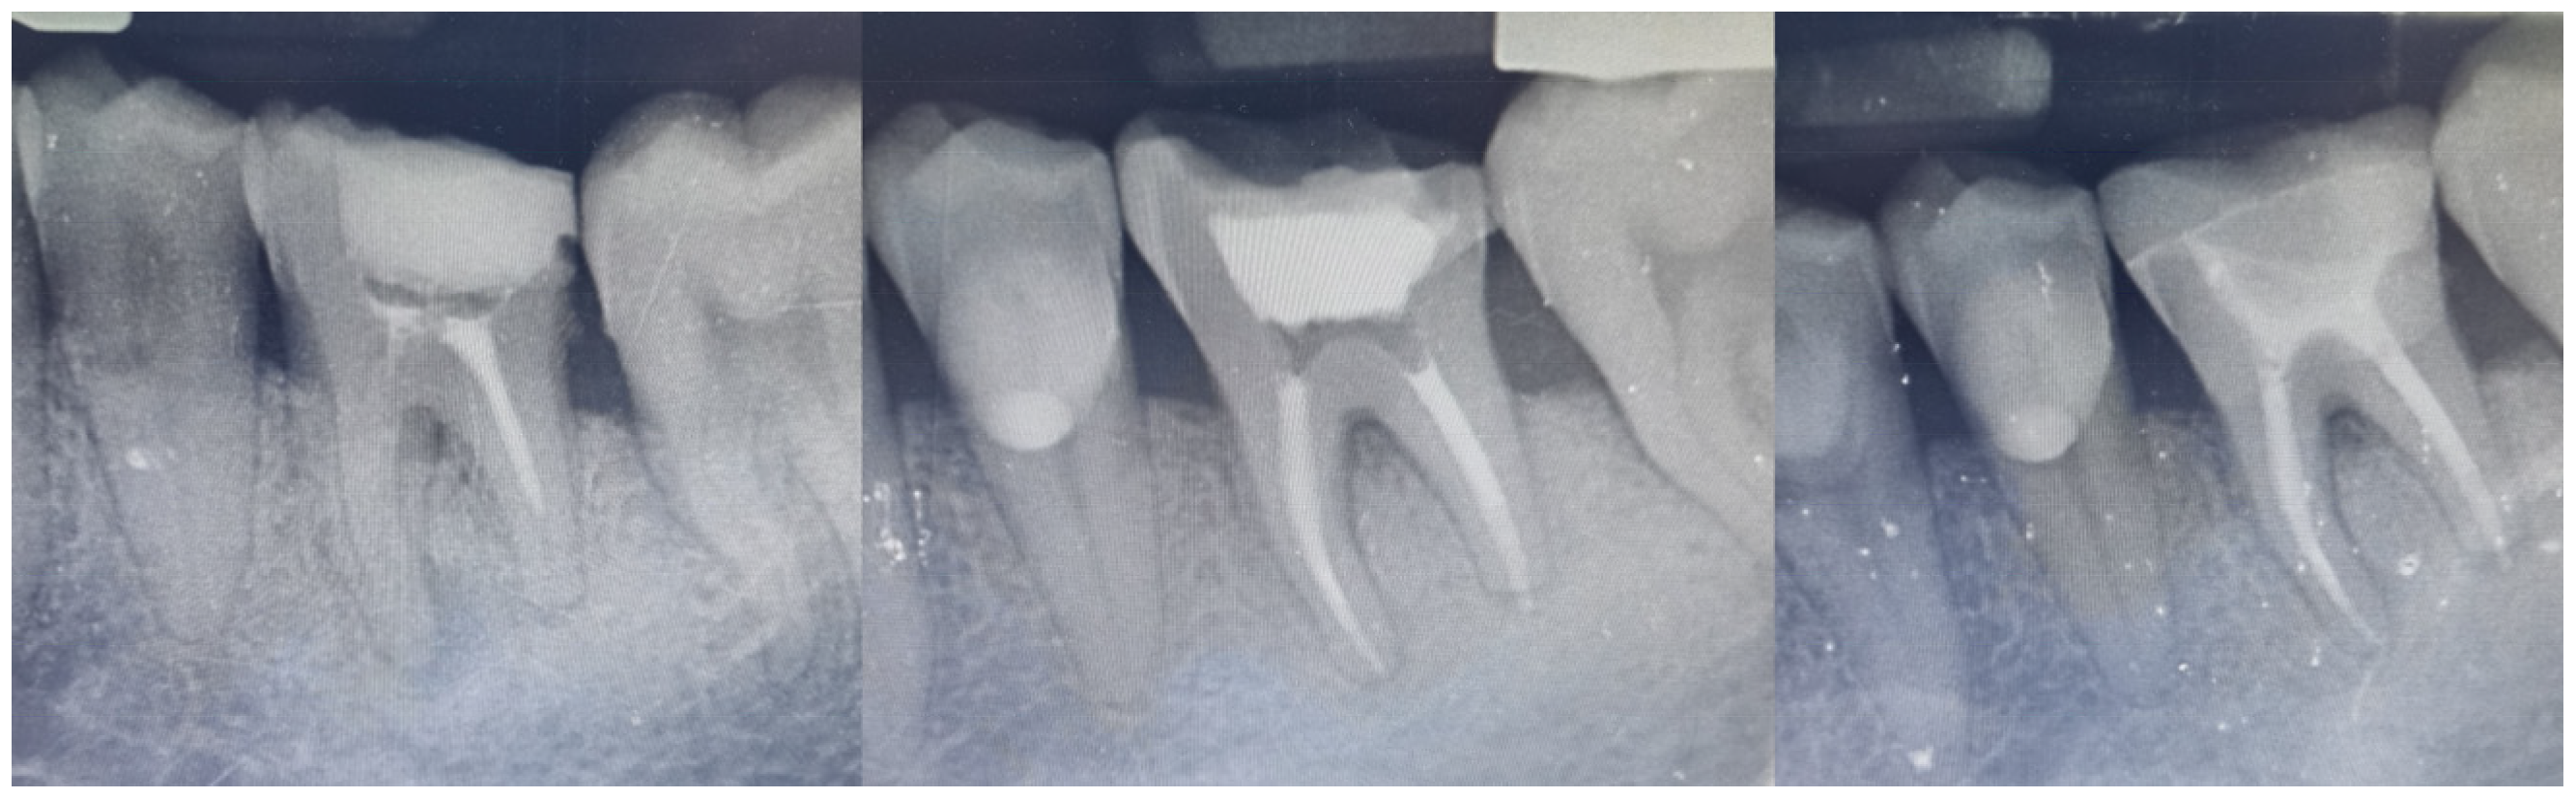

The Modified US Public Health Service (USPHS) criteria were used for the objective evaluation of the restoration at the five-year recall [19]. Two authors (E.P. and T.K.S.), other than the one who delivered the endocrown (D.P.), were chosen to evaluate the restoration, and both of them rated the restoration as “Alfa” in all of the included parameters, which corresponds to the ideal clinical situation. Radiographic evaluation (Figure 10) did not reveal any pathology or defective areas.

Figure 10. Radiographic images at baseline, after the RCT reintervention and at the 5-year recall.